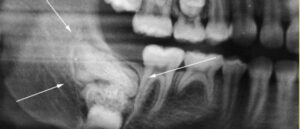

Фиброма на нижней и верхней челюсти

Существуют различные виды опухолей, которые развиваются в лицевой области. Одной из таких считается фиброма челюсти. Заболевание приносит своему обладателю эстетический и физический дискомфорт. Хоть причины появления образований в челюсти неясны, врачи успешно проводят их лечение. Недуг не несет угрозу для жизни, так как состоит из доброкачественных клеток, но важно знать об этой проблеме и вовремя …